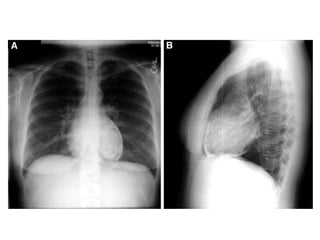

• Pericardial effusion------------

tampnade

• However, patients with a large pericardial

effusion, a hemodynamically significant

pericardial effusion, a suspicion of a

bacterial or neoplastic etiology, or

evidence of constrictive pericarditis

should be evaluated for invasive

therapies, such as pericardial

drainage and/or pericardiotomy.